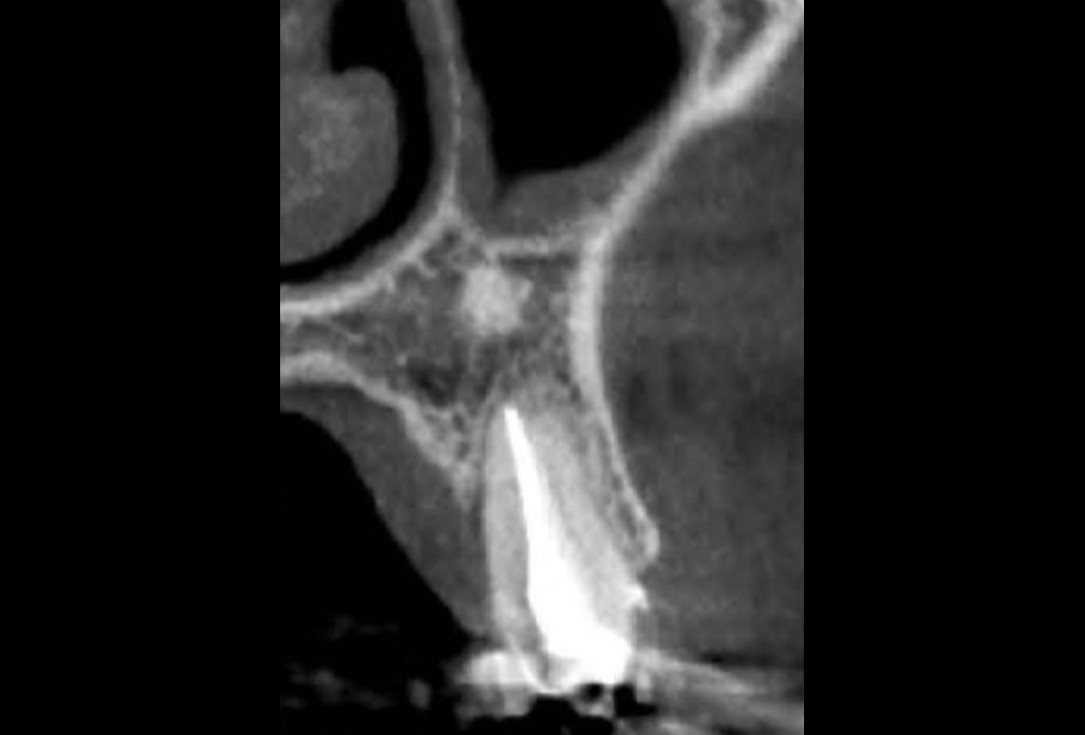

01/16 - Initial clinical situation: 9 mm pocket depth associated with root fractureFull bone regeneration in extraction socket augmented with maxgraft® and Jason® membrane – Dr. C. Landsberg

02/16 - Advanced loss of palatal boneFull bone regeneration in extraction socket augmented with maxgraft® and Jason® membrane – Dr. C. Landsberg